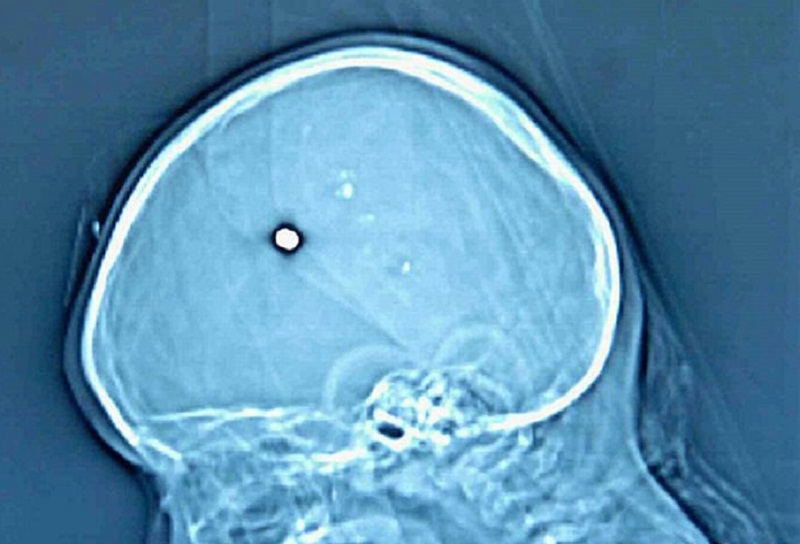

Юный житель Брянской области пять лет ходил с пулей в голове – пока голова всё-таки не заболела

Житель Брянской области Александр 19 лет от роду обратился в поликлинику с сильной головной болью – врачи обнаружили, что он натурально ходит с пулей в голове.

Житель Брянской области Александр 19 лет от роду обратился в поликлинику с сильной головной болью – врачи обнаружили, что он натурально ходит с пулей в голове. Причём, как, выяснилось, уже пять лет, пишет Baza .

Когда Саше было 14 лет, он вместе со старшим братом Никитой гостил у бабушки. Как-то парни решили пострелять из пневматической винтовки, и одна пуля, срикошетив, попала Саше в голову. Родители узнали об этом тогда же, но мальчик уверил, что у него ничего не болит, поэтому идти к врачам не нужно.

Теперь под Новый год голова Александра напомнила ему, что в ней уже несколько лет находится пуля. У него разболелась голова, он пришёл в местную поликлинику, затем его отправили в областную больницу, где врачи диагностировали у него инородное тело в правой теменной области и подострую гематому в правом полушарии. Его жизни ничего не угрожает, пулю скоро вытащат.